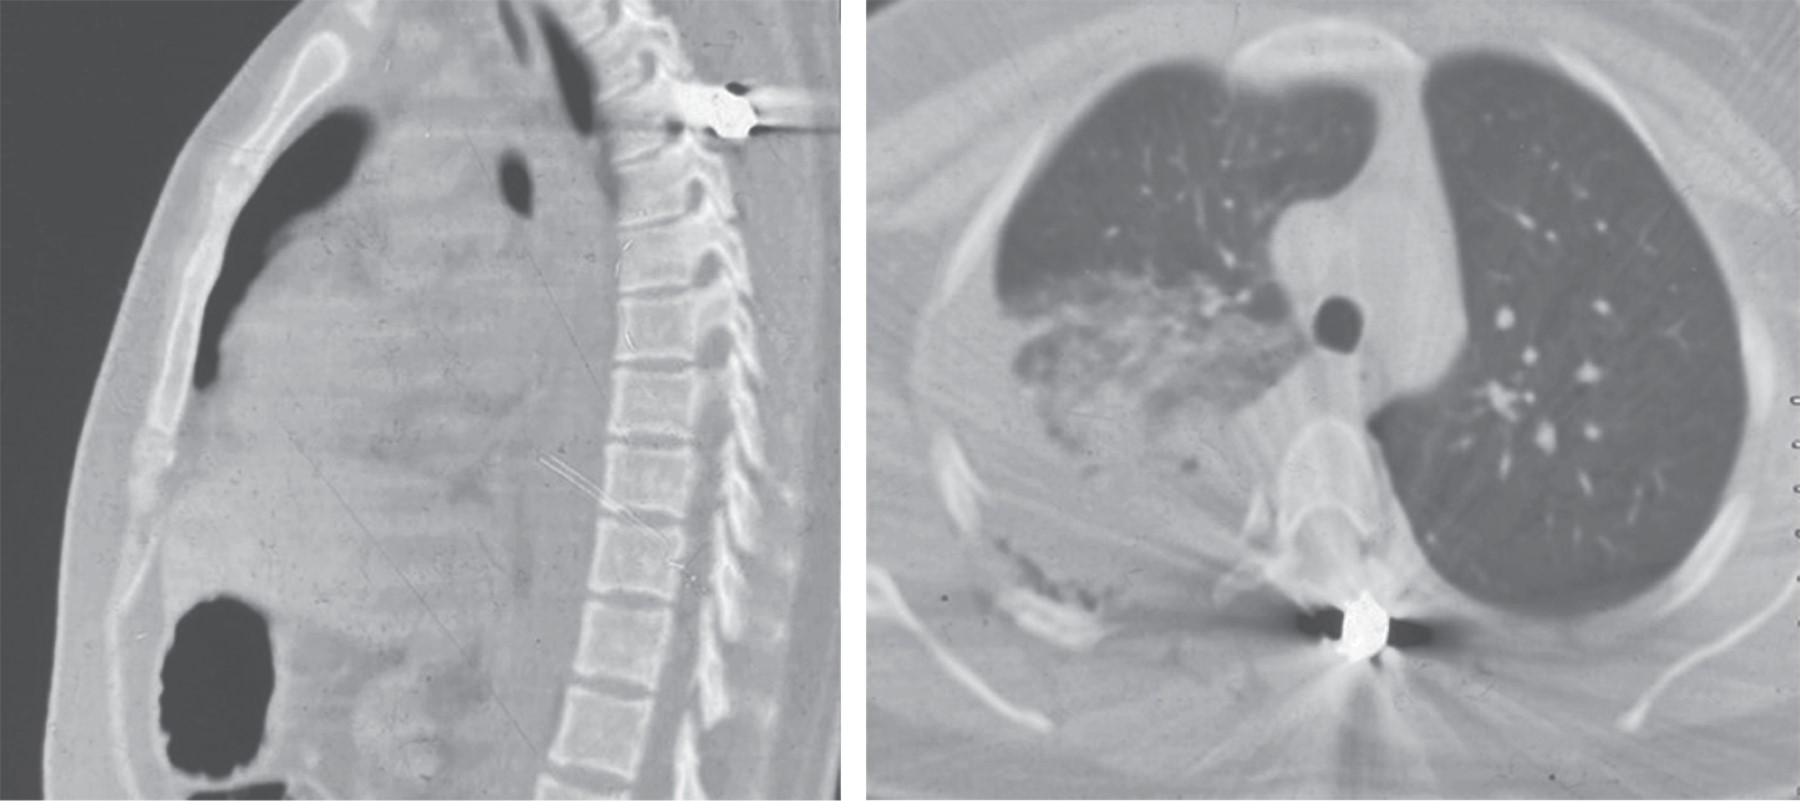

Paciente femenino de 26 años, sin antecedentes de importancia para el padecimiento actual, sufre agresión por lesión directa con proyectil de arma de fuego. Ingresa inicialmente a un hospital comunitario donde se encuentra paciente con orificio de entrada a nivel de hombro derecho sin orificio de salida. La paciente presentó dificultad respiratoria, pérdida de la función sensitiva y motora de las extremidades inferiores. Posteriormente fue trasladada a un hospital de tercer nivel, donde se diagnostica hemotórax derecho, fractura de escapula derecha y fractura de segunda y tercera vértebras torácicas (AO T2:A0, T3:B1, N3. M1). En un inicio fue manejada con colocación de sello pleural derecho, inmovilizador universal para hombro y se decidió manejo quirúrgico para las fracturas vertebrales. La radiografía simple mostró fractura de láminas de T3 y apófisis espinosa de T2 con alojamiento del proyectil a nivel de láminas de T3. La tomografía axial simple mostró solución de continuidad ósea a nivel de T2 con afección de pedículo y lámina derecha sin desplazamiento y a nivel de T3 fractura multifragmentada de láminas y apófisis espinosa con invasión a conducto raquídeo, así como afección facetaria bilateral (Figura 1). No se realizó resonancia magnética por la presencia del proyectil que estaba alojado a nivel de la lámina de T3. La paciente obtuvo una categoría B en su valoración neurológica inicial (ASIA), presentando preservación del tono del esfínter anal; hiporreflexia rotuliana y aquílea bilateral, reflejo plantar conservado bilateral, fuerza muscular 0/5 (Daniels) de L2 a S1 bilateral y anestesia de L2 a S1 bilateral. Los estudios paraclínicos prequirúrgicos mostraron glucosa de 80 mg/dl, urea 21.4 mg/dl, BUN 10 mg/dl, creatinina 0.5 mg/dl, leucocitos 12.63 × 103/µl, neutrófilos 67.7%, linfocitos 22.9%, hemoglobina 9.9 g/dl. Hematocrito 30.9%, plaquetas 213.0 × 103/µl, tiempo de protrombina 15.6 s tiempo de tromboplastina parcial 25 s INR 1.12. Los laboratorios postquirúrgicos mostraron glucosa de 102 mg/dl, urea 40.7 mg/dl, BUN 19 mg/dl, creatinina 0.5 mg/dl, leucocitos 15.65 × 103/µl, neutrófilos 76.8%, linfocitos 13.4%, hemoglobina 11.9 g/dl, hematocrito 37%, plaquetas 346.0 × 103/µl, tiempo de protrombina 14.9 s, tiempo de tromboplastina parcial 24.1 s INR 1.06.

Figura 1